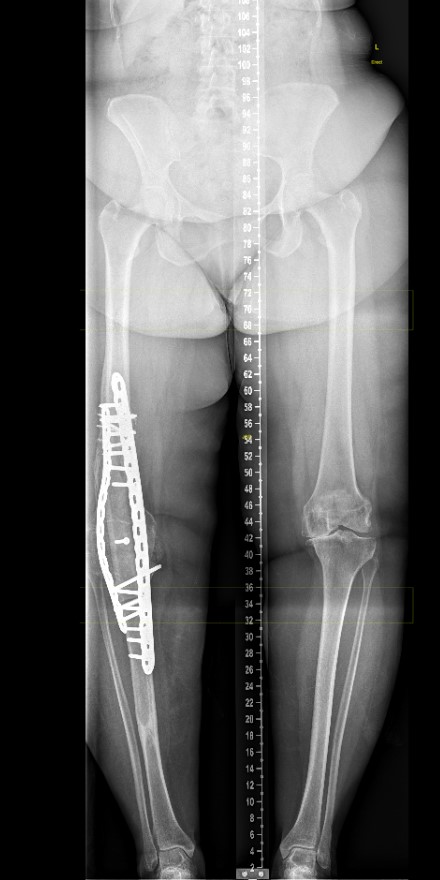

2. Double plating

Dual plates